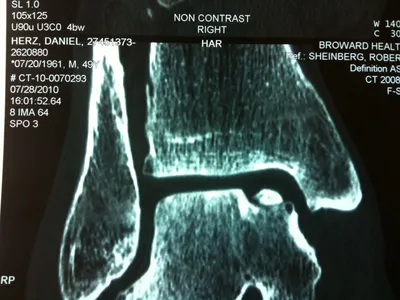

Series of Pics of Microfracture of large OCD of the Talar Dome

Action shot of microfracture of talus OCD.

Bleeding of OCD after microfracture.